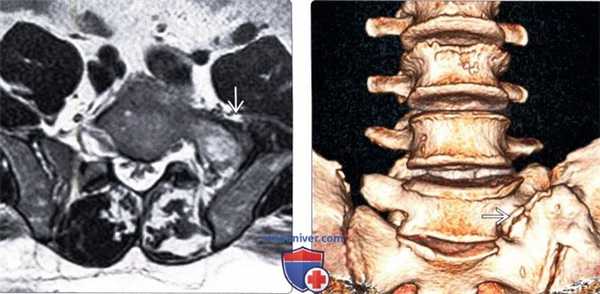

3. МРТ при синдроме Бертолотти:

• Т1-ВИ:

о МР-анатомия, соответствующая переходному каудальному поясничному сегменту

• Т2-ВИ:

о Гиперинтенсивность Т2-сигнала в области неоартроза и прилежащих участках костного мозга, согласно литературным данным, не является характерной особенностью данного состояния

(Слева) Т2-ВИ, аксиальная проекция: признаки переходного пояснично-крестцового сегмента с частичной сакрализацией слева.

(Справа) На представленной фронтальной трехмерной КТ-реконструкции отмечается наличие аномального псевдосочленения тела каудального поясничного позвонка с крестцом и подвздошной костью.